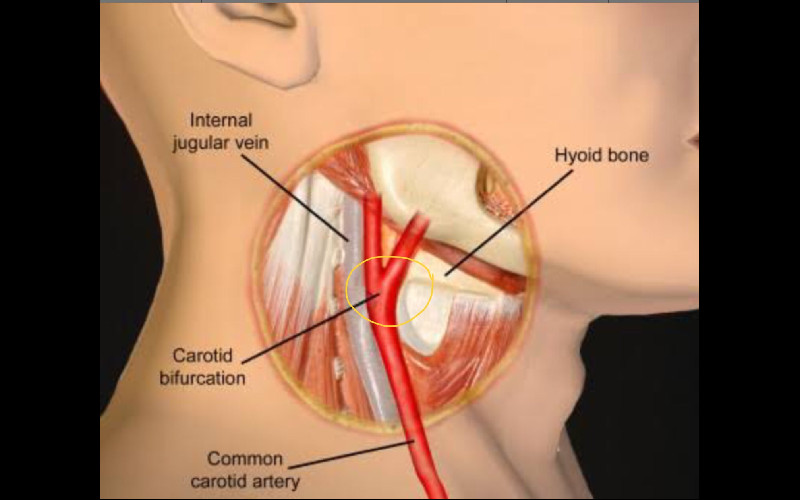

Arteri karotis adalah pembuluh darah utama yang memasok darah ke otak dan seluruh area kepala. Setiap individu memiliki dua arteri karotis komunis, yang terletak di sisi kanan dan kiri leher. Arteri ini kemudian bercabang menjadi arteri karotis interna, yang terutama memasok darah ke otak, dan arteri karotis eksterna, yang memasok darah ke wajah, kulit kepala, dan leher.